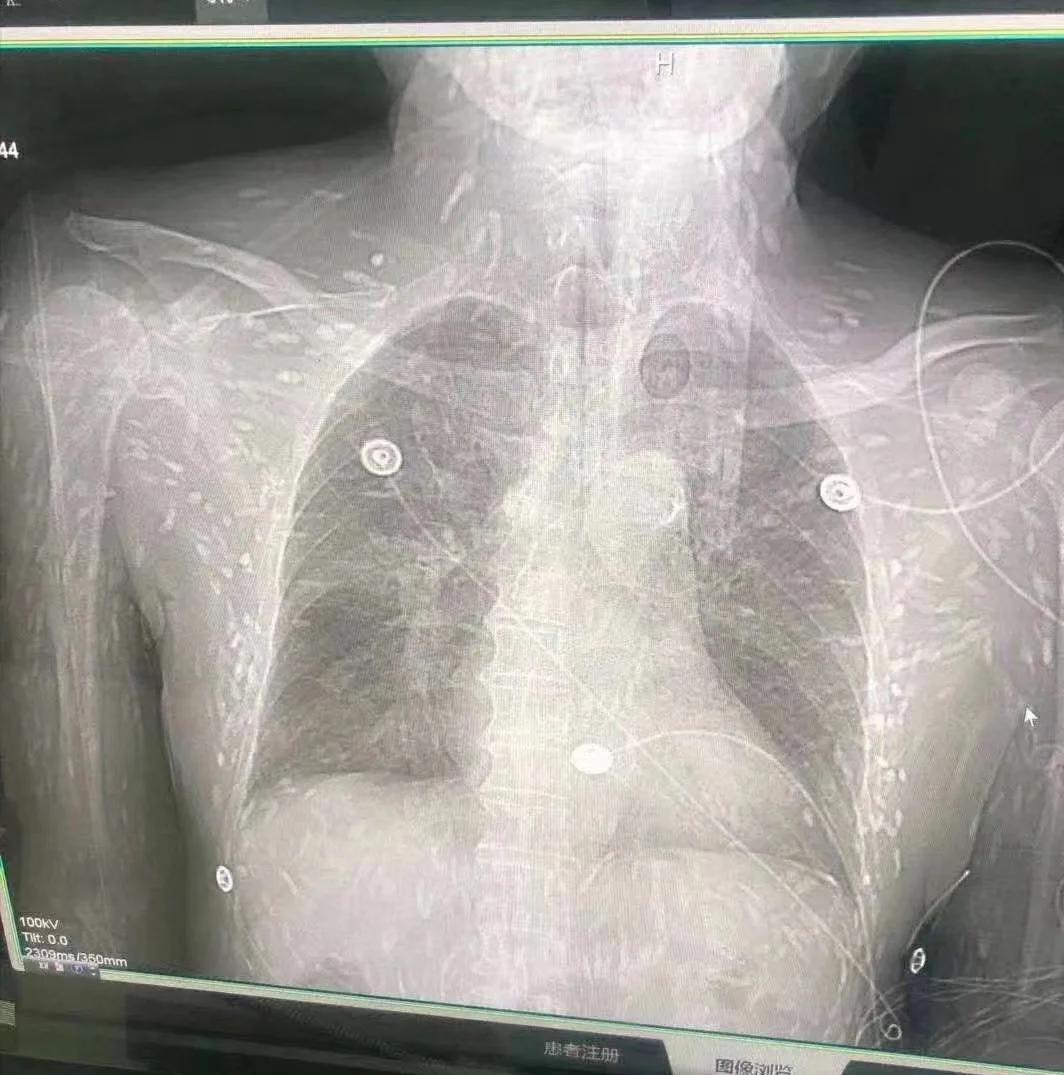

图片过于恶心,请谨慎观看,手不要太快。